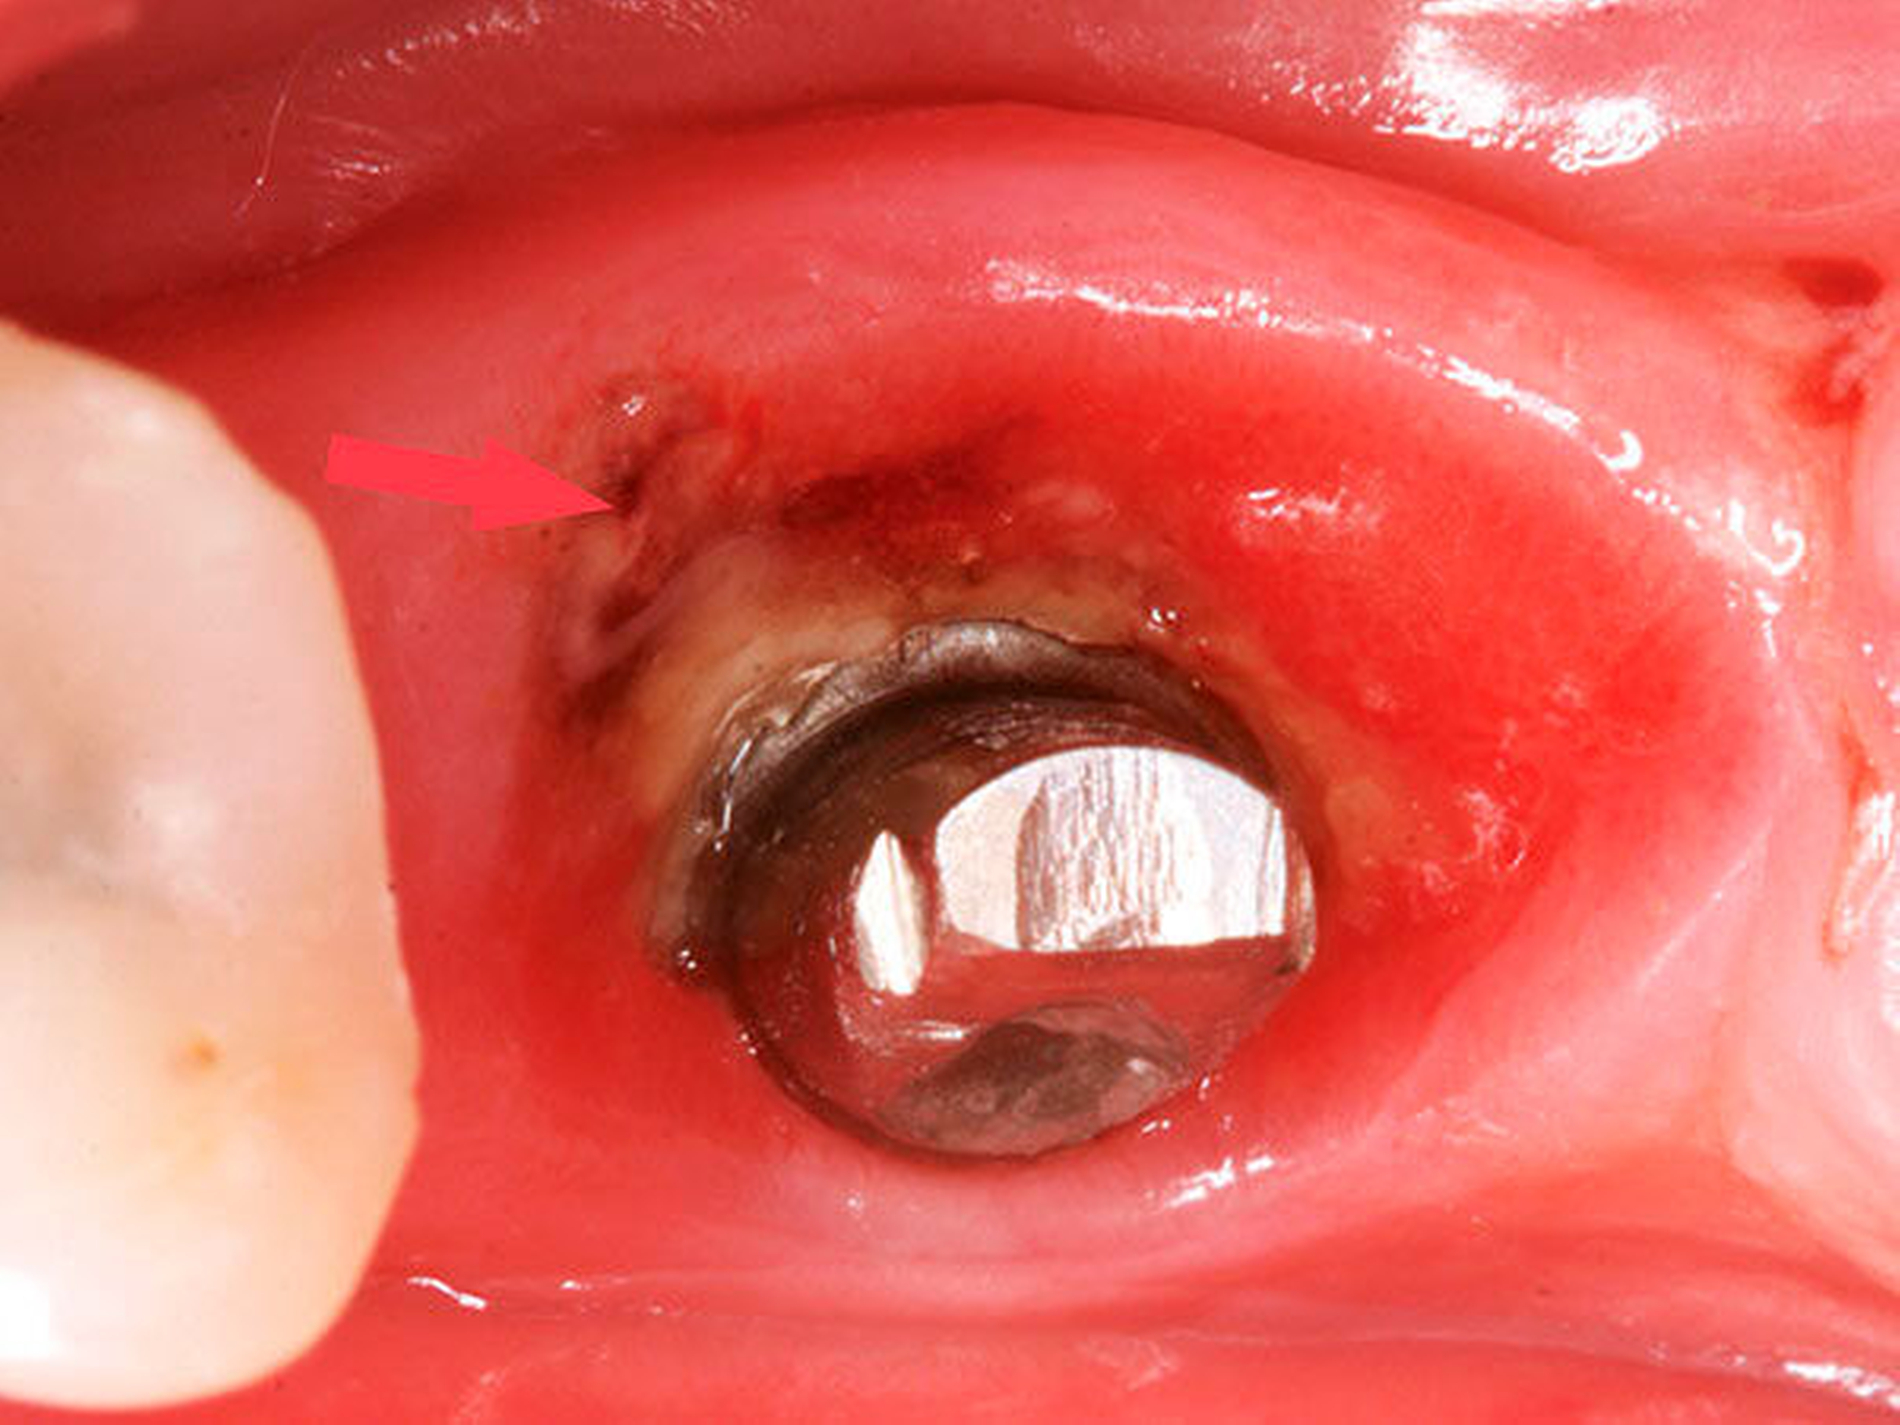

Nach einigen Monaten klagten Patienten über Blutungen an den Implantaten. Der klinische Befund ergab in allen Fällen Bluten auf Sondierung und Suppurationen im Bereich der Implantate (Abbildung 1). Zur Ursachenanalyse wurde in diesen Fällen die festsitzende Konstruktion einschließlich der Abutments revidiert. In allen Fällen wurde unterhalb der Abutments, im Bereich der Implantatschulter Zement gefunden (Abbildung 2).